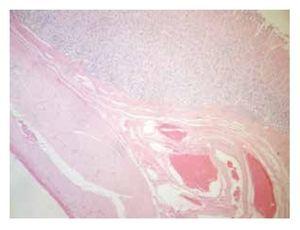

Descripción microscópica: cambios histológicos observados en la región fúndica y antral del modelo porcino a las 24 horas y a los tres días postinyección endoscópica de cinco soluciones (Figuras 1 y 2).

Figura 1. Cuadrantes con ácido hialurónico, glicerol, solución salina 0.9% y sangre. Submucosa con marcada rarefacción y edema, además de escasos elementos inflamatorios no específicos y fibroblastos.